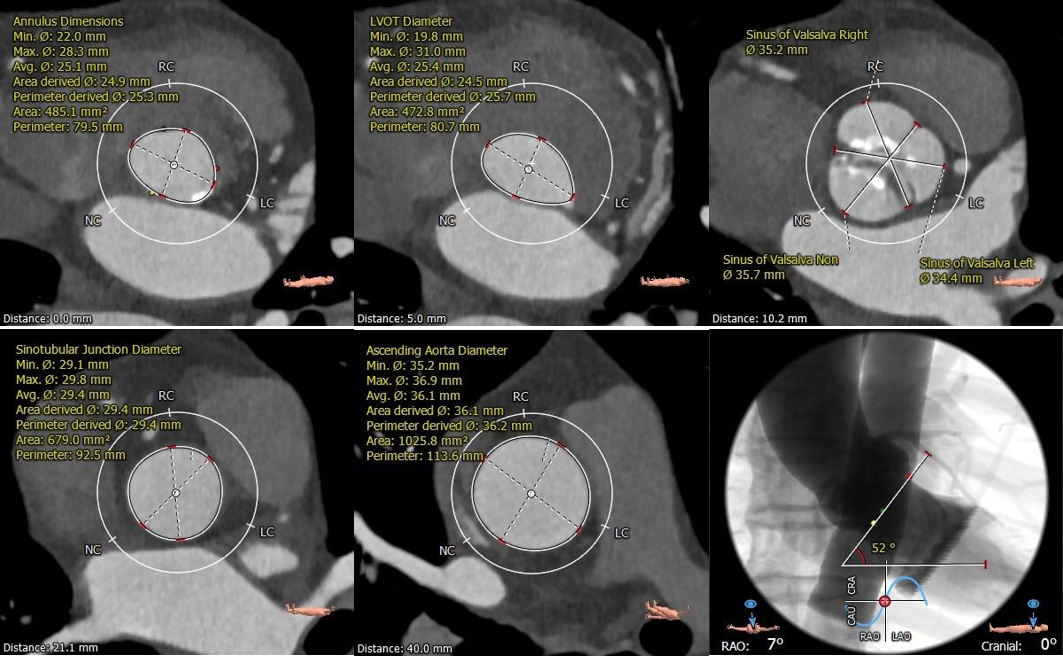

术前CT评估:

主动脉根部评估:

冠脉评估:

钙化评估:

重度钙化,左冠窦钙化延伸至LVOT水平

血管入路评估: